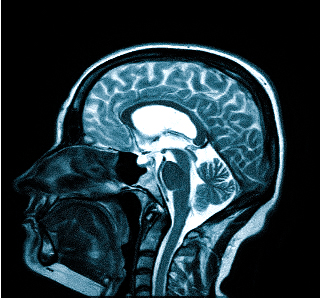

Для процедуры пациент ложится на стол-транспортер, который заезжает в томограф — сканирующее устройство. На время обследования пациент остается в трубе и должен сохранять неподвижность для получения четкого изображения. Процедура занимает от 15 минут.

Специальной подготовки не требуется, но необходимо предупредить врача о клаустрофобии, так как это может быть противопоказанием. Если во время МРТ вы почувствуете недомогание, сообщите об этом специалисту, проводящему обследование МРТ головы.

МРТ — это неинвазивный метод, основанный на создании изображений с помощью радиоволн и мощного магнитного поля, что абсолютно безопасно для здоровья. Головные боли после процедуры могут быть вызваны нервным перенапряжением в ожидании результата и являются индивидуальной реакцией на стресс. Магнитно-резонансное сканирование длится около 30-40 минут, и важна максимальная неподвижность пациента. Шум аппарата можно уменьшить с помощью наушников с музыкой. Во время процедуры не возникает болевых ощущений. При необходимости можно повторить МРТ для отслеживания ситуации. Некоторые впечатлительные пациенты отмечают усиление головной боли после исследования, но специалисты считают, что это связано с основным заболеванием или самовнушением. Цефалгией функционального или психогенного генеза занимаются неврологи, психиатры или терапевты, а МРТ помогает выявить изменения органического характера.